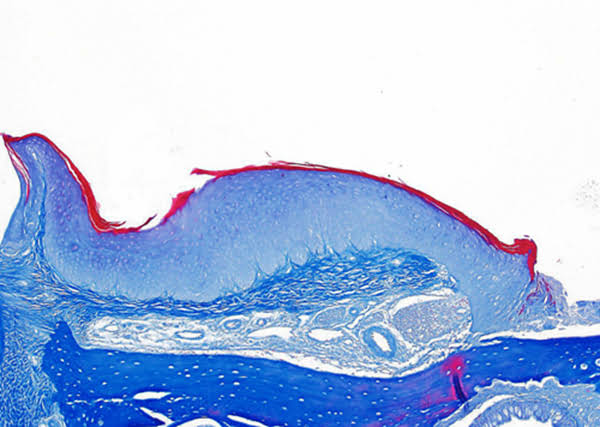

為促進科學(xué)文化發(fā)展,活躍專委會的科技人文氛圍,培養(yǎng)科研工作者的創(chuàng)新意識,激發(fā)他們發(fā)現(xiàn)美、創(chuàng)造美的熱情和興趣,本次年會特別增加了一項“生命的藝術(shù)——首屆年度顯微圖片展”活動。在專委會發(fā)出征稿通知之后,來自全國近20 所院校的師生積極響應(yīng),共投稿顯微攝影作品125 幅。經(jīng)以王松靈院士為主席的九位審讀專家組成員在線上線下的認真審閱和討論,從圖片的原創(chuàng)性、科學(xué)性和藝術(shù)性三個方面進行綜合考量,最終確定年度圖片1 幅,年度提名圖片20 幅。在此匯集成冊,與各位同仁分享、交流。

這些作品幾乎均為創(chuàng)作者在日??蒲泄ぷ髦幸圆煌募夹g(shù)手段捕捉到的微觀生命瞬間,科學(xué)的“透鏡”似乎為我們展現(xiàn)出一幅幅藝術(shù)的“魔幻”,一邊是細胞、分子層面的微觀抵達,另一邊好似一塊既陌生又熟悉的“優(yōu)詩美地”。這里,本是科學(xué)嚴謹?shù)念I(lǐng)地,因為其關(guān)乎生靈,便開啟人們自由逸放的審美思緒。在此,我們驚嘆中國古代哲學(xué)體系中“天人合一、道法自然”的天道規(guī)律。原來早于現(xiàn)代科學(xué),這種“盡精微而致廣大”的宇宙觀便已根植于我們生存的大地。感謝各位作者以他們現(xiàn)代技術(shù)的視野,為我們定格生命律動的瞬間,張揚蓬勃的藝術(shù)活力。換一個視角,生命的風景便呈現(xiàn)“天地人”的和諧和統(tǒng)一,換一種思路,生命的哲學(xué)便更能詮釋苦難與幸福的非凡境遇。